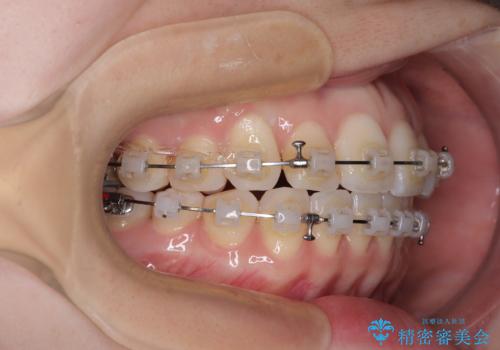

- クリアブラケット

補助装置を用いて上顎臼歯を後方移動させ、歯列を整えながら前歯部の接触を図ることとしました。

舌の突出癖改善のためのトレーニングを指導しながら、ワイヤー装置にて矯正治療を行うこととしました。